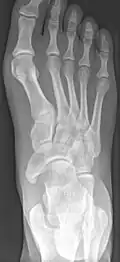

X-ray of the foot showing an accessory navicular bone

An accessory navicular bone is an accessory bone of the foot that occasionally develops abnormally in front of the ankle towards the inside of the foot. This bone may be present in approximately 2-14% of the general population and is usually asymptomatic.[1][2][3] When it is symptomatic, surgery may be necessary.

Radiological images